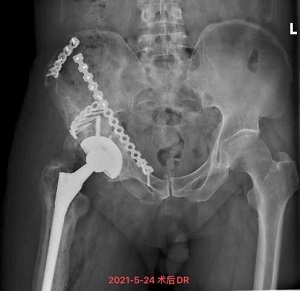

5月13日,饱受关节疼痛困扰的严爷爷在家人陪同下到我院就诊并入住关节骨病科。董克芳主任团队在仔细评估讨论后,制定了详细手术方案,并于5月21日为严嗲嗲进行了右人工髋关节翻修术,术后当日即指导其开始进行功能锻炼,1周后,严爷爷可下地行走,关节疼痛感也没了。28日,主管医生林少如反复叮嘱老人家一些注意事项后,严爷爷在家人陪同下出院回家了。